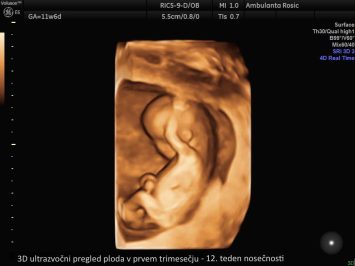

Zgodnja UZ potrditev nosečnosti Nuhalna svetlina in DHT z licenco FMF NIFTY test 3D/4D ultrazvočni pregled ploda Ultrazvočna meritev materničnega vratu Ultrazvočna kontrola plodove rasti, lege in teže Ultrazvočna kontrola ploda ter Dopplerska meritev pretokov Morfologija ploda Četverni hormonski test Streptokok B Kardiotokografija Galerija ultrazvočnih posnetkov